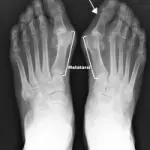

Sintomi alluce valgo e cura: operazione per alluce valgo (piede). Nuovo intervento chirurgico